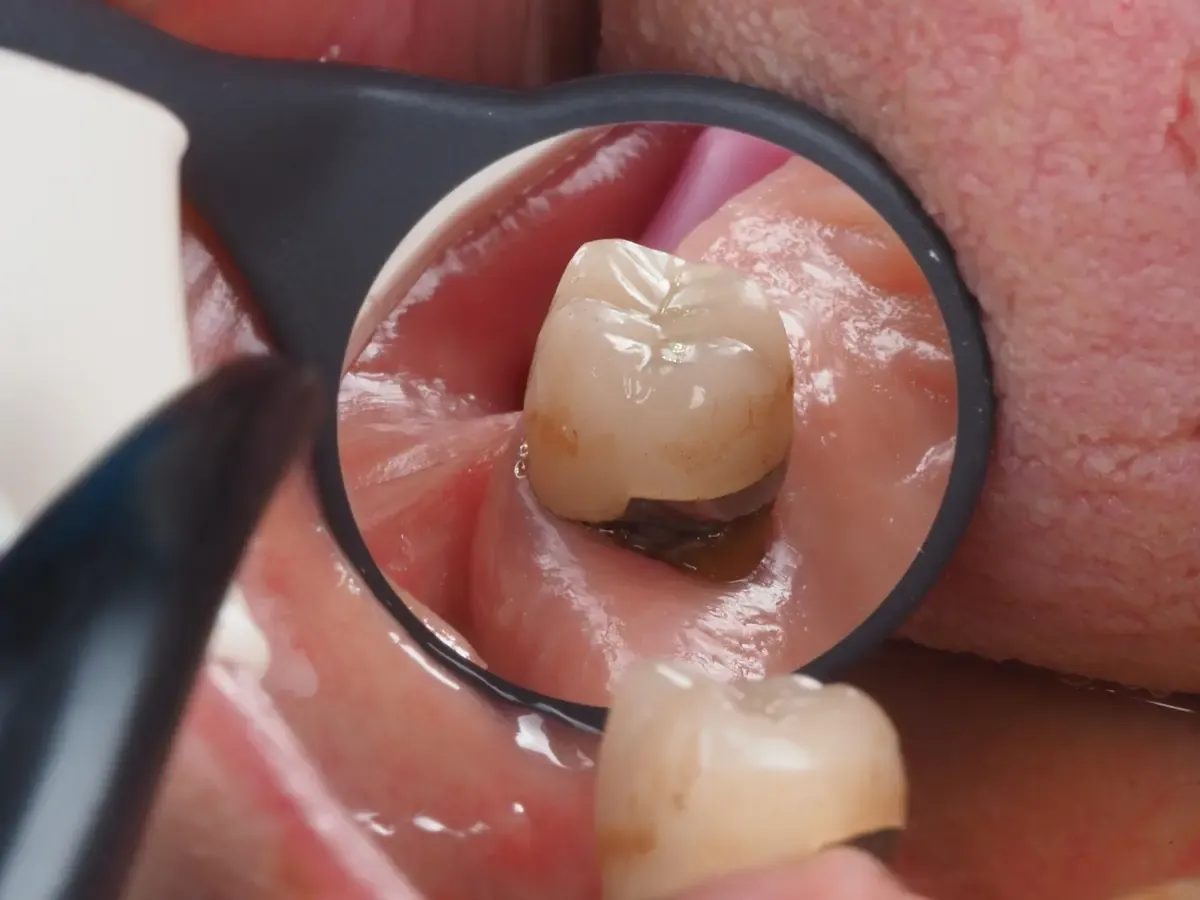

Objawy problemów z zębem na sztyfcie i kiedy szukać pomocy

W przypadku zęba na sztyfcie, istnieje kilka objawów, które mogą wskazywać na to, że konstrukcja może zawodzić. Wczesne rozpoznanie tych symptomów jest kluczowe dla uniknięcia poważniejszych problemów zdrowotnych. Do najczęstszych objawów należą: ból w okolicy zęba, ruchomość zęba, a także obrzęk dziąseł. Jeśli zauważysz którykolwiek z tych objawów, niezbędne jest natychmiastowe skontaktowanie się z dentystą.

Ignorowanie tych symptomów może prowadzić do poważnych komplikacji, takich jak infekcje czy utrata zęba. Dlatego, jeśli ząb na sztyfcie zaczyna sprawiać problemy, warto jak najszybciej zasięgnąć porady specjalisty. Pamiętaj, że regularne kontrole u dentysty również pomagają w wczesnym wykrywaniu potencjalnych problemów i utrzymaniu zdrowia jamy ustnej.

Jak rozpoznać, że ząb na sztyfcie wymaga interwencji?

Istnieje kilka konkretnych objawów, które mogą wskazywać na potrzebę interwencji stomatologicznej. Przede wszystkim, ruchomość zęba na sztyfcie powinna być sygnałem alarmowym. Jeśli ząb zaczyna się poruszać, to oznacza, że może być problem z jego stabilnością. Ponadto, intensywny ból lub dyskomfort w okolicy zęba również wskazują na konieczność wizyty u dentysty.

Inne znaki, na które warto zwrócić uwagę, to obrzęk dziąseł oraz wydzielina ropna w okolicy zęba. Te objawy mogą świadczyć o infekcji, która wymaga natychmiastowego leczenia. W przypadku zauważenia jakichkolwiek z tych symptomów, nie zwlekaj z wizytą u specjalisty, aby uniknąć poważniejszych komplikacji zdrowotnych.